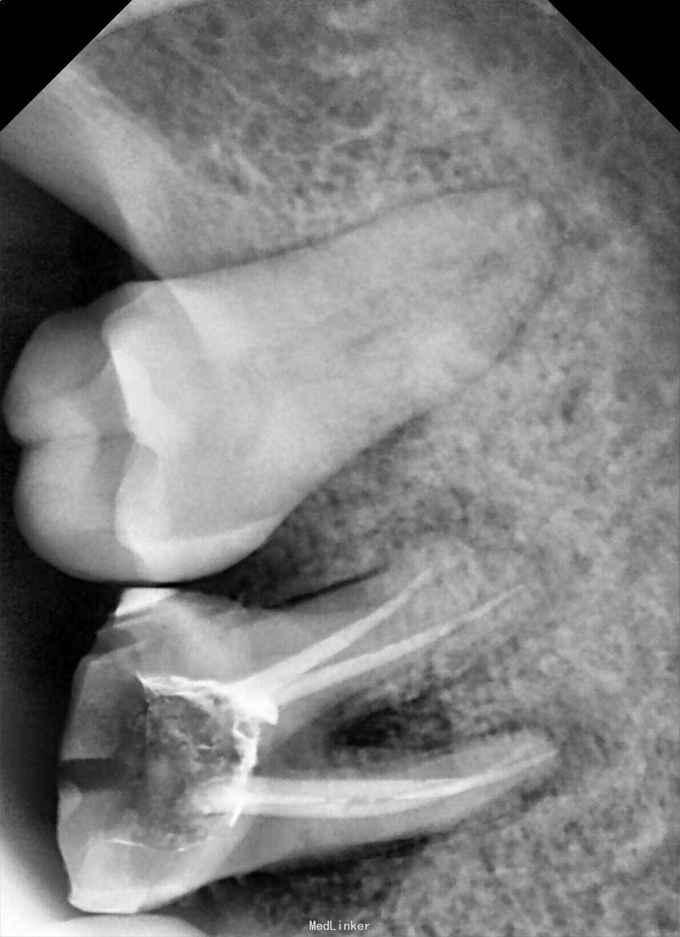

检查:36牙残冠,开髓洞型,叩(+),松(-) 辅查:36牙远中根管口有异物,根尖暗影

诊断:36牙慢性根尖周炎 治疗:36牙探及根管口④,远颊根管口阻塞,选用尖头金刚砂车针去除部分髓底,暴露断针头部,超声(P尖)逆时针振荡,直到断针松动,然后用血管钳取出断针,疏通根管,机扩,充填,术后1个月复查,根尖暗影范围略有缩小